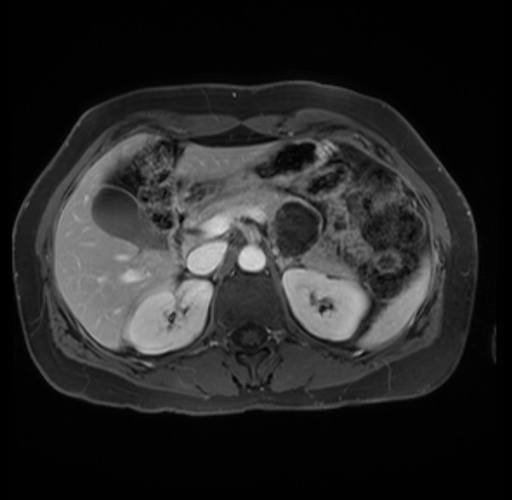

Imaging Analysis

Look through the patient's CT scan to identify any areas of concern for the necessary procedure.

Based on your CT findings, which issue(s) are present and would give reason for "planned slowing down moment(s)" in this case?